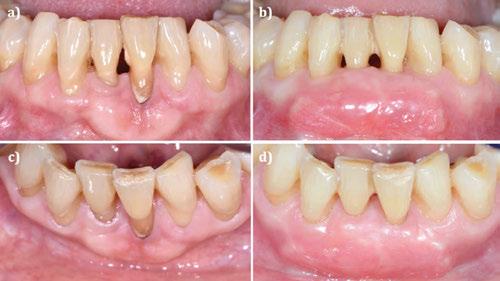

Figura 1. Caso clínico 1. Situación clínica basal de una paciente que presenta recesiones gingivales con pérdida de inserción interproximal en el quinto sextante. A la exploración se observa una profundidad de sondaje incompatible con salud en centro-vestibular del diente en posición de 41, presumiblemente combinado con una dehiscencia ósea.

CASO CLÍNICO 1 (FIGURAS 1-7)

Paciente de 32 años de edad que acude a la consulta preocupada por la situación de su diente en posición de 41. Le preocupa tanto a nivel de salud como a nivel estético. Además, refiere incapacidad para llevar a cabo un correcto cepillado de esa zona e hipersensibilidad dental.

A la exploración clínica presenta una recesión RT3 (23) en el diente en posición de 41. Además, carece de una banda de encía queratinizada adecuada (≥2mm) y presenta una reducción significativa de la